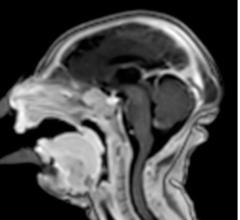

Philips announced the introduction of a suite of magnetic resonance (MR)-based software applications dedicated to neurology, which will debut at the Radiological Society of North America's (RSNA) 102nd Scientific Meeting and Annual Assembly in Chicago. With these introductions for its Ingenia family of digital MRI systems, Philips is reinforcing its global leadership in Neuro MR software applications, providing radiologists with the necessary tools to resolve complex health questions and explore new territories in neurology.

Taking music lessons increases brain fiber connections in children and may be useful in treating autism and attention deficit hyperactivity disorder (ADHD), according to a new study. The data will be presented at the 2016 annual meeting of the Radiological Society of North America (RSNA), Nov. 27-Dec. 1 in Chicago.